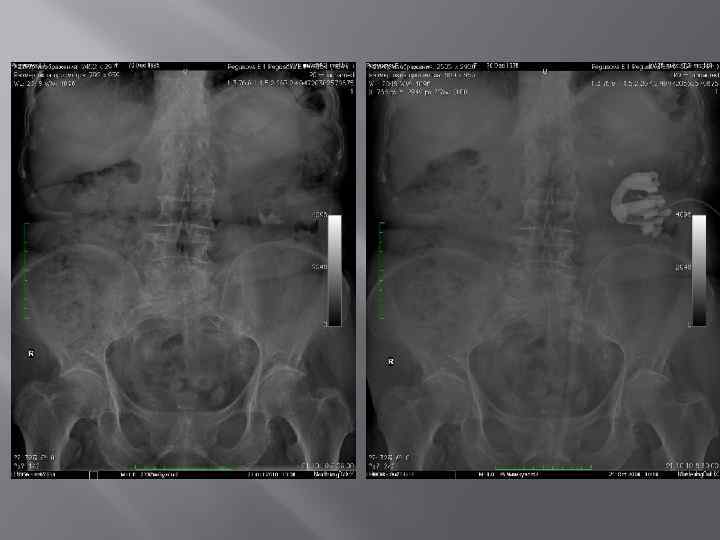

Камни в мочевом пузыре